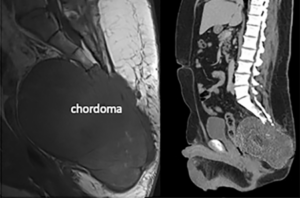

این نوع نادر تومور استخوانی معمولاً در پایه جمجمه یا در استخوانهای تحتانی ستون فقرات ایجاد میشود. به طور کلی به کندی رشد می کند و به ندرت به سایر نواحی بدن گسترش می یابد. با این حال، حذف کامل آن می تواند چالش برانگیز باشد و احتمال عود در محل اولیه وجود دارد.